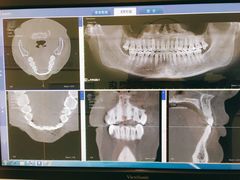

• Dr.Z dental仁康种植矫正中心

• -Dr.Z dental仁康种植矫正中心